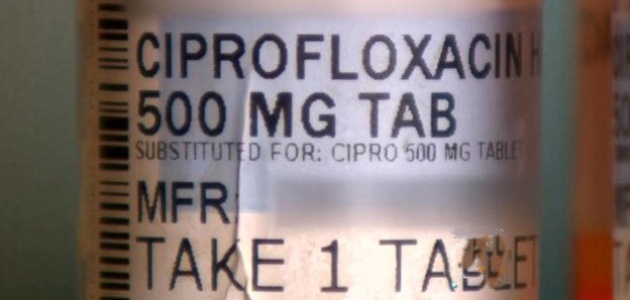

FDA-approved fluoroquinolones include levofloxacin (Levaquin), ciprofloxacin (Cipro), ciprofloxacin extended-release tablets, moxifloxacin (Avelox), ofloxacin and gemifloxacin (Factive).